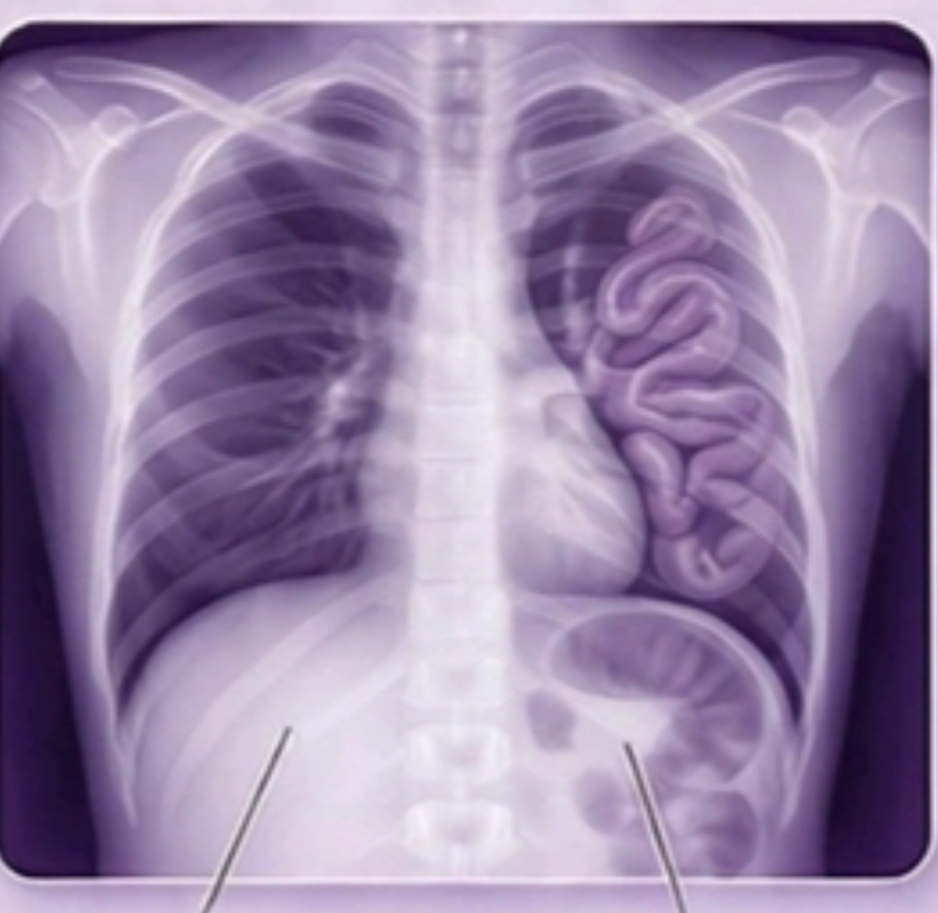

- Photorealistic Infographics of Various Causes of Neonatal Respiratory Distress. Free preview

Congenital Diaphragmatic Hernia (CDH)

Detailed chapters on EA+TEF, CDH, CLH, CPAM & BPS, and Posterior Choanal atresia for in-depth understanding.